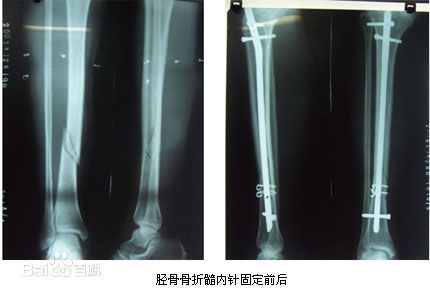

胫骨中1/3稳定型骨折:横形骨折、短斜形骨折、假关节。

-

胫骨中部60%长度内的不稳定性骨折:干骺端附近的骨折、长螺旋形骨折、节段性骨折、粉碎性骨折、骨折伴骨缺损。

多用于胫骨中段骨折。尽管也可用于胫骨近端和远端骨折,但并发症发生率较高,易发生畸形愈合。